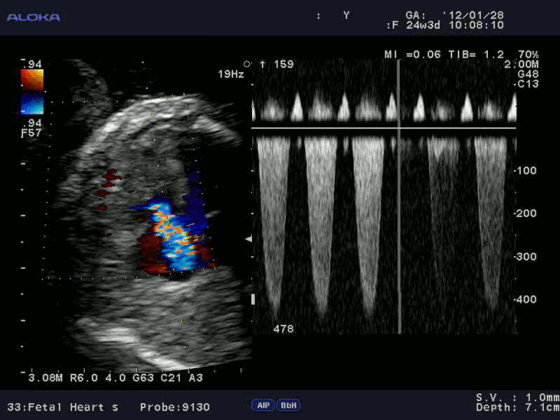

Для облегчения выявления турбулентного движения (завихрений) существует порог скорости, выше которого происходит изменение цвета (во многих аппаратах это зелены). «Мозаичный» узор на участке турбулентного потока позволяет легко установить регургитацию (смену направления движения), что помогает определить степень недостаточности клапанов.

Допплерэхокардиография позволяет измерить все вышеперечисленные параметры, которые очень важны при оценке детской сердечной патологии (врожденные пороки) без использования инвазивной процедуры — катетеризации сердца. Помимо этого, назначение эхокардиографии с допплеровским анализом ребенку не несет никакой угрозы по сравнению с компьютерной томографией, где используется рентгеновское излучение.